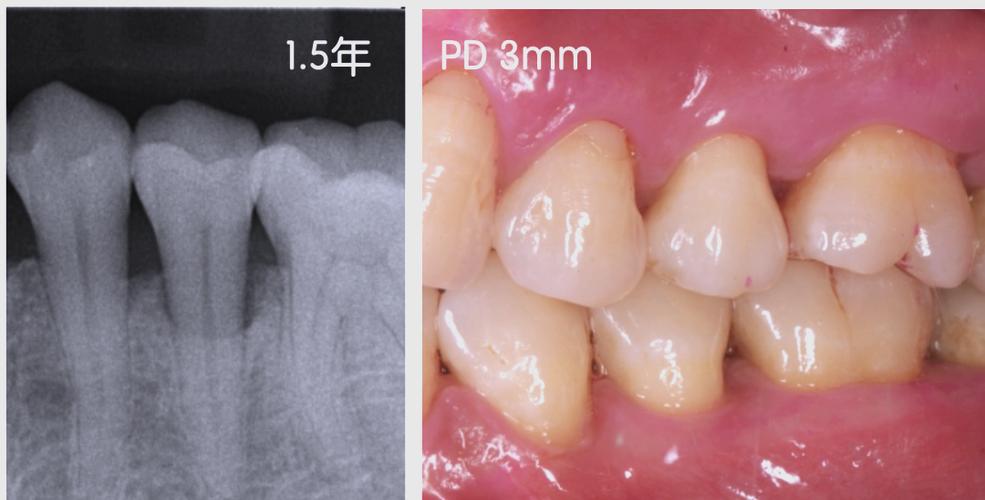

预期效果:成功者可见骨密度增加(CBCT示骨缺损区高密度影),牙齿松动度减轻,牙龈形态改善,前牙区美学效果提升;种植术前植骨者可满足种植体植入条件。